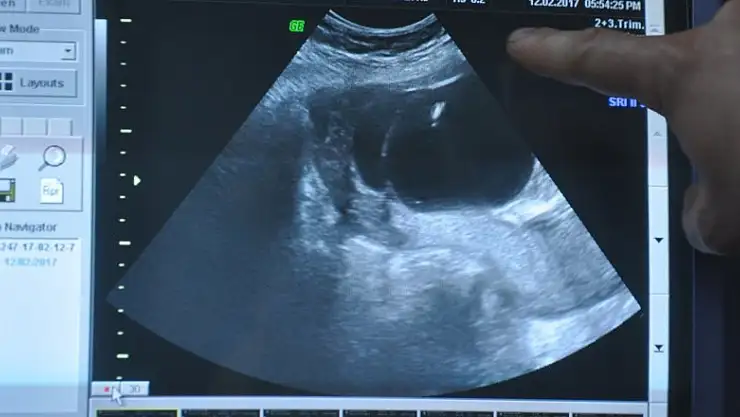

Meram Tıp Fakültesi Kadın Hastalıkları ve Doğum Ana Bilim Dalı Öğretim Üyesi Prof. Dr. Ali Acar, yapılan kontroller sonrası bebeğe anne karnındayken müdahale kararı aldı. Bebek küçük ve ikiz olduğu için oldukça riskli olan idrar torbası ameliyatı, Acar ve ekibi tarafından başarıyla gerçekleştirildi.

"Çocuğun idrar torbası dolu, idrar çıkışı kapalıydı. Her iki böbreği de sıvı dolmuştu. Anne karnında bebeklerin kaybedilme ihtimalleri yüksekti. İkiz gebeliğe yapılan nadir ve riskli işlemlerden birini gerçekleştirdik. Bu şekilde her iki çocuğun da yaşaması sağlandı. Operasyonu çocuk 320 gram ağırlığında 18 haftalıkken gerçekleştirdik. Bir ucu idrar torbasına, diğer ucu da bebeğin karnının dışına yerleştirilen 1,5 milimetre çapında, 10 santimetre boyundaki 'şant' adı verilen ince uzun elastik, teflon bir kateter ile çocuğun idrarını çıkarması sağlandı. Bu şekilde böbrekler rahatlatıldı. Anne karnında ameliyat olduğu için zorluğu olan bir operasyondu. İyi bir ekip çalışmasıyla gerçekleştirilen operasyon sonrası çok şükür gebelik normal seyrinde devam ediyor."